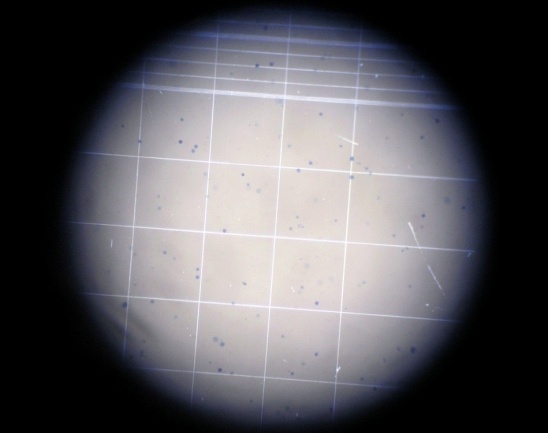

3. Cancer cell count

About 0.1 ml of fluid was withdrawn from the peritoneal sac of each and every mouse with the help of sterile syringe. The fluid was diluted with 0.8 ml of ice-cold normal saline or sterile Phosphate Buffer solution and 0.1 ml of Trypan blue (0.1 mg/ml). The total numbers of the living cells were counted using haemocytometer.

Cell count = No of cells Dilution/(Area × Thickness of liquid film)

Viable cell count (fig. 19)

Normal control |

Cancer control |

Positive control |

Treatment control-FMCuNPs |

Fig. 19: Viable cell count of in vivo anticancer activity of FMCuNPs